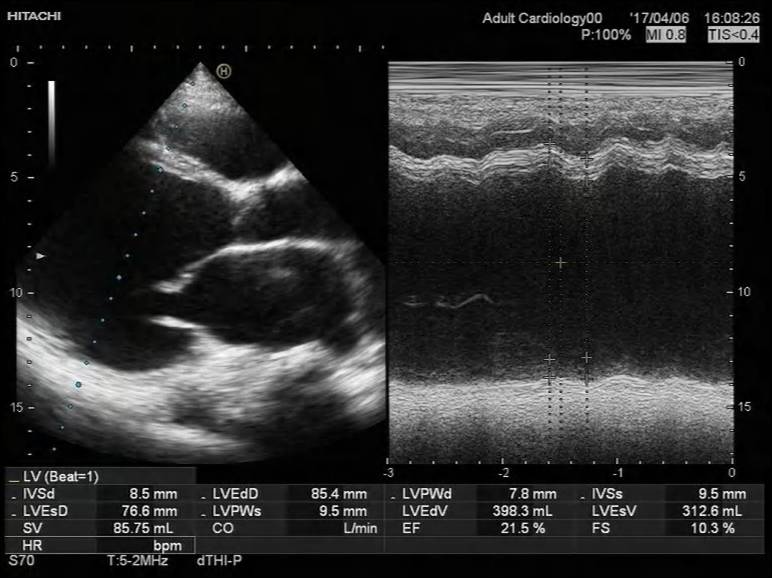

2017-4-7心超检查报告:

符合扩张型心肌病声像图改变:

◆1、左室壁运动弥漫性减弱 左心及右房大 ,EF 21%,左室缩末内径 76mm,舒末内径85mm。

◆ 2、二尖瓣前瓣瓣尖轻微对合错位并二尖瓣重度关闭不全(瓣环扩张所致)

◆3、 三尖瓣中度反流、主动脉瓣微量反流 左室收缩舒张功能减退 肺动脉高压(中度)